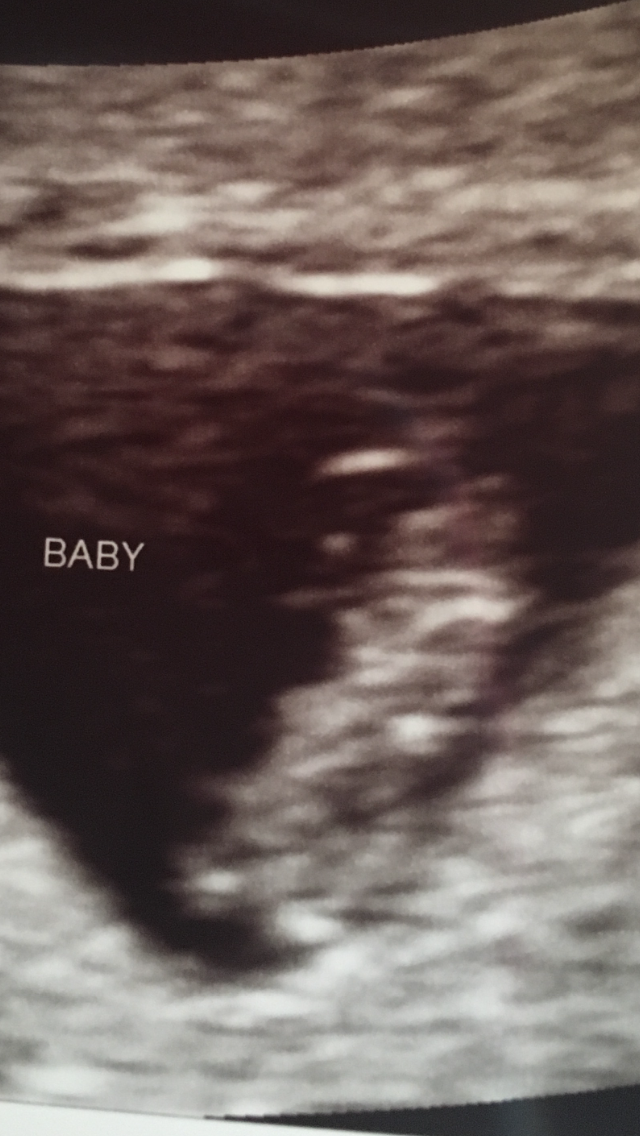

I had my second u/s on Tuesday at 8 weeks and 6 days. The baby is still measuring three days behind but they have not changed my edd. It was great to see how big the baby has gotten and to see its heart still beating. I go back on the 23 for some genetic testing and I get an u/s at that appointment, which was a great surprise to hear that. The equipment at the new place I have to go to is so much better than what my doctor has. Im hoping I can actually hear the heart beat at that appointment. I have not been able to hear it or to know how many bpm it is. But here is my little bean!

Btw I have no clue what those white lines are and neither does my doctor.